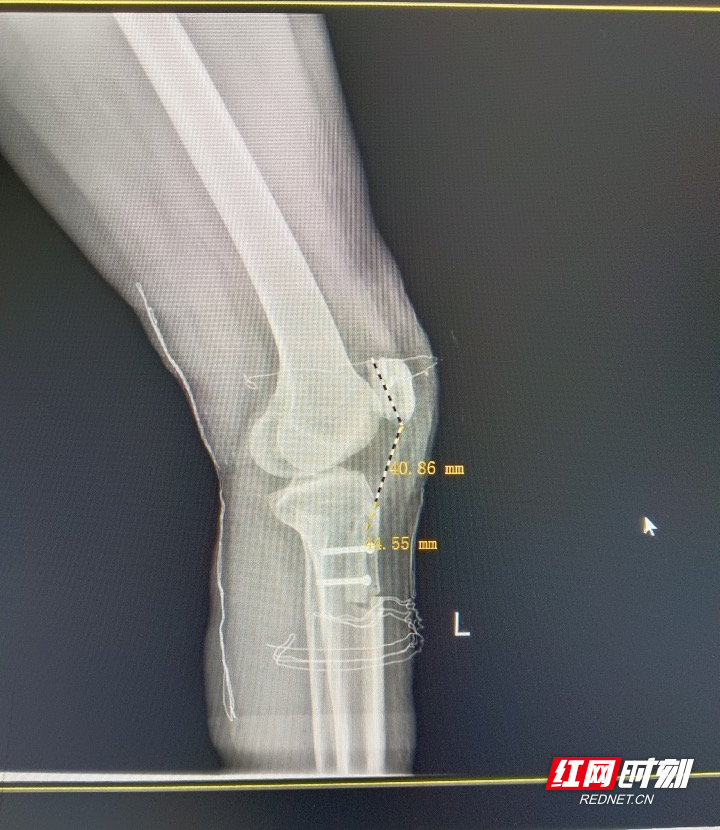

术后,胫骨结节转位后髌骨高度恢复正常。

“常规保守治疗已难以稳定她的膝关节。”湘潭市中医医院运动医学科主任成勇峰介绍,团队通过膝关节镜下髌骨股骨内侧韧带重建术及胫骨结节转位术,一方面重建内侧韧带作为“静态稳定器”,另一方面通过截骨转位,调整髌骨力线,从根本上纠正脱位。手术全程微创,术后髌骨复位牢固,高度恢复正常,膝关节终于找回“轨道”。